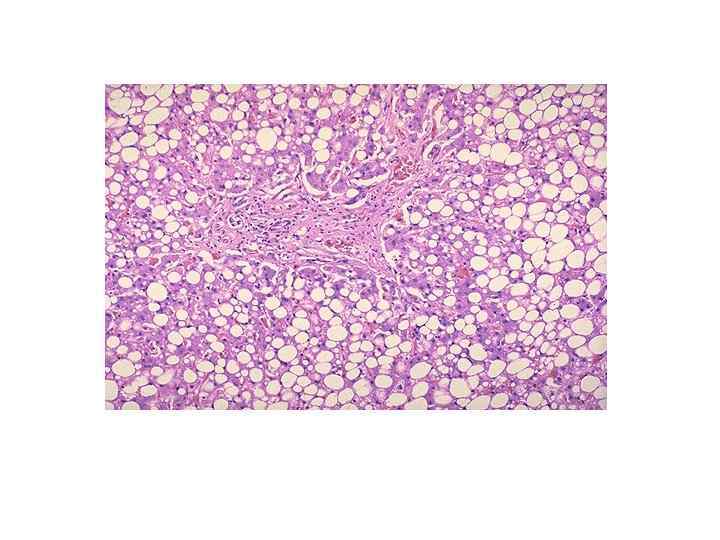

Алкогольная болезнь печени • - стеатоз (наиболее частая форма) • - острый алкогольный гепатит • - веноокклюзионная болезнь

Алкогольная болезнь печени (морфология) • -микровезикулярная жировая дистрофия (менее благоприятна) • -макровезикулярная жировая дистрофия • -очаговые интралобулярные некрозы с преимущественно нейтрофильной инфильтрацией • -алкогольный гиалин (тельца Маллори)